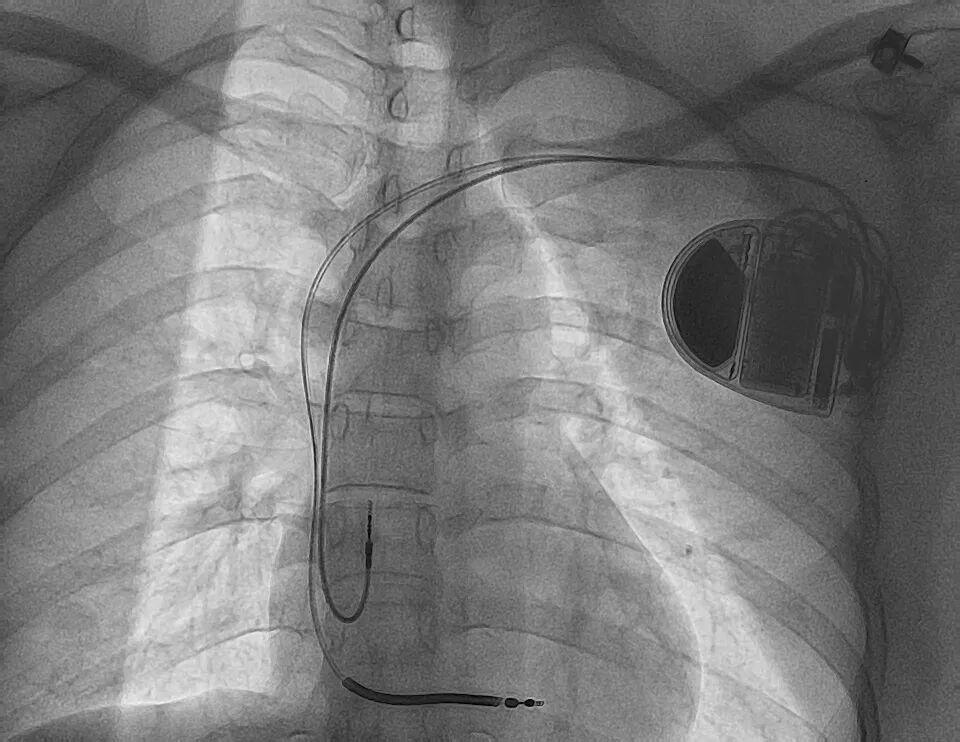

经过充分术前准备,张安吉主任团队为刘女士开展了手术。手术在局部麻醉下进行,医生精准地将电极导线通过静脉植入她的右心室,并将ICD脉冲发生器埋藏在左胸前皮下。这台设备能24小时实时监测心脏节律,一旦检测到室速、室颤等恶性心律失常,会立刻自动发放电击除颤。